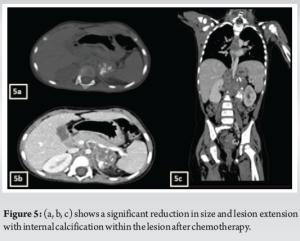

A 3-year-old female was brought to the pediatric orthopedic department with complaints of swelling over her left leg for 2 months. The swelling was insidious in onset, progressive in nature, associated with pain which was aggravated by movement, more at night, and associated with fever and local rise of temperature. According to the mother, weight loss and loss of appetite were noted. No history of abdominal pain. An X-ray of the left thigh was requested. It revealed an ill-defined subtle expansile lytic lesion in the diaphysis and distal metaphysis region of the left femur with the suggestion of lamellated (onion peel) and sunburst (in a few areas) types of periosteal reaction (Fig. 1). No evidence of fracture was noted. Laboratory results were as follows; white blood cell – 7220 cells/μL, hemoglobin – 6.8 g/dL (decreased), hematocrit – 24%, platelets – 190,000/μL, C-reactive protein (CRP) – 81.5 mg/L (raised) and lactate dehydrogenase (LDH) – 467.99 U/L (raised). The differential diagnosis of primary bone tumor (Ewing’s sarcoma > osteosarcoma) and osteomyelitis was considered initially. (High Resolution Sonography)left thigh was done, which revealed soft tissue showing significant vascularity on color Doppler with associated spiculated sunburst type of periosteal reaction (Fig. 2). A provisional diagnosis of primary bone tumor was made and as a part of metastatic screening, ultrasonography of the abdomen was advised. It revealed a large ill-defined heterogeneous retroperitoneal mass crossing the midline, encasing the aorta and its branches. The mass was seen insinuating beneath the aorta, lifting it off the vertebral column. Multiple enlarged pre/para-aortic lymph nodes and bilateral common, external, and internal iliac vessels were noted (Fig. 3). To further characterize the abdominal mass, the contrast-enhanced computed tomography (CECT) chest with the abdomen covering the thigh was done. It revealed a large heterogeneous solid mass lesion epicenter in the left suprarenal region measuring 10 × 6.6 × 11.6 cm in maximum orthogonal dimensions and crossing the midline. It shows multiple amorphous and chunky calcifications within. The mass is heterogeneously enhanced with areas of necrosis and is encasing and displacing the abdominal aorta. The left adrenal gland was not seen separately and mass is seen displacing the left kidney inferiorly and laterally. Multiple enlarged heterogeneously enhancing retroperitoneal lymph nodes are seen along with bony metastatic lesions (Fig. 4). Based on these findings, the primary diagnosis of left suprarenal neuroblastoma with multiple lymph-nodal and bony metastasis was made. Ultrasound (USG)-guided tru-cut biopsy of the left suprarenal mass was performed, which revealed small round blue cell tumor cells arranged in sheets and nests. Bone marrow trephine biopsy taken from bilateral posterior superior iliac spine revealed metastatic deposits of small round blue cell tumor. These cells were positive for synaptophysin, chromogranin, and cluster of differentiation-99 and negative for leukocyte common antigen confirming the diagnosis of neuroblastoma (Fig. 6). Eight cycles of neo-adjuvant chemotherapy were given to the patient. A metaiodobenzylguanidine scan post-chemotherapy revealed no residual bony metastasis. Positron emission tomography-computed tomography (PET-CT) was also done which revealed a non-fludeoxyglucose tissue mass noted in the left suprarenal region with an unremarkable musculoskeletal system. Follow-up CECT abdomen with the chest was done to assess chemotherapy response and for pre-operative planning which revealed a significant reduction in size and extent of the lesion with a significant reduction in number and size of retroperitoneal lymph nodes (Fig.5,7). Surgery was done and the residual lesion was removed. The patient is now on follow-up.